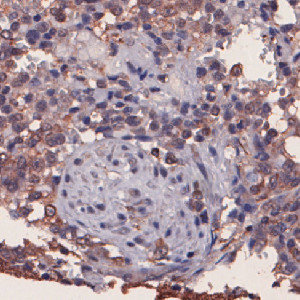

Nuclei surrounded by CD74 negative, low and intermediate staining.

The “10130 – CD74, Melanoma, TME” APP detects nuclei and classifies them as either negative, 1+, 2+ or 3+ based on the CD74 staining expression present in each nucleus’ vicinity.

To identify the nuclei, the APP performs a two-stage polynomial blob filtering on a blue-enhanced feature image and delimits them using local linear filtering. Each pixel with DAB staining is classified as low, mid and high based on the intensity and grouped together locally. Each nucleus is then classified based on its surroundings in the order of 3+, 2+, 1+ and negative to emphasize the strongest staining present in each nucleus’ vicinity.